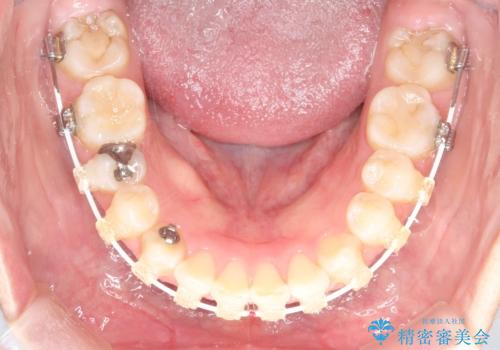

- 矯正装置

- 審美装置

- 2年9ヶ月

- 10-30回